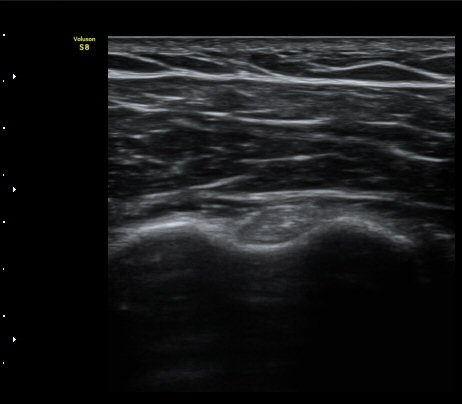

±Ø»ó°Ç Á¾´Ü¸é°Ë»ç¿¡¼­ ´ë°áÀý °Ç ºÎÂøºÎ¿¡ Àú¿¡ÄÚ °Ç °á¼ÕÀÌ °üÂûµÊ

(focal hypoechoic defect of ssupraspinatus tendon at greater tuberosity with

longitudinal scan of subscapularis tendon) »çÁø 4, 5, 6